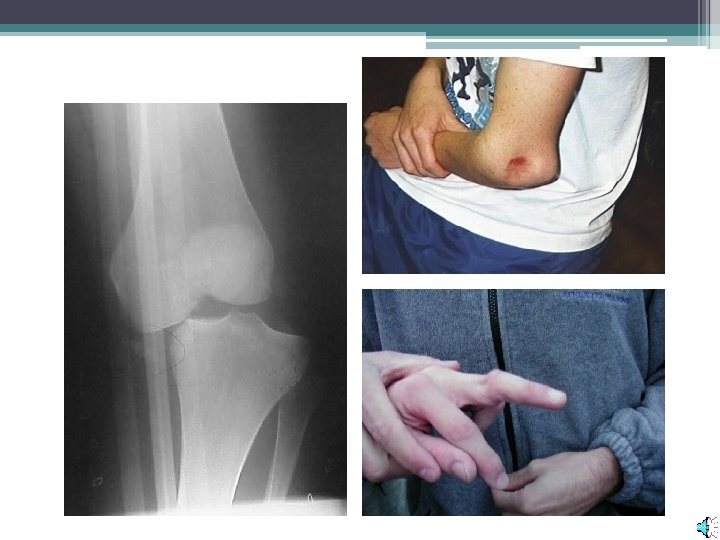

• Sprains are a stretching/tearing of the ligament tissue. ▫ Occur when a joint is forced into an abnormal position

• Dislocations are caused when a bone is completely displaced from its joint.

• A simple or closed fracture is caused when the bone breaks internally but does not come through the skin.

• An open or compound fracture projects through the skin. ▫ Increased bleeding and risk of infection.

• Greenstick fractures do not break through the entire bone. ▫ More likely in children, due to a greater portion of cartilage. • Similar to pulling a branch off a living tree.

Prepatellar bursitis. Inflammation of the patellar bursae directly over the patella.

Dislocation (luxation) • Forceful displacement of an articulating bone to an abnormal position, usually accompanied by damage to tendons, ligaments, the articular capsule, or other structures. • A subluxation is a partial dislocation.